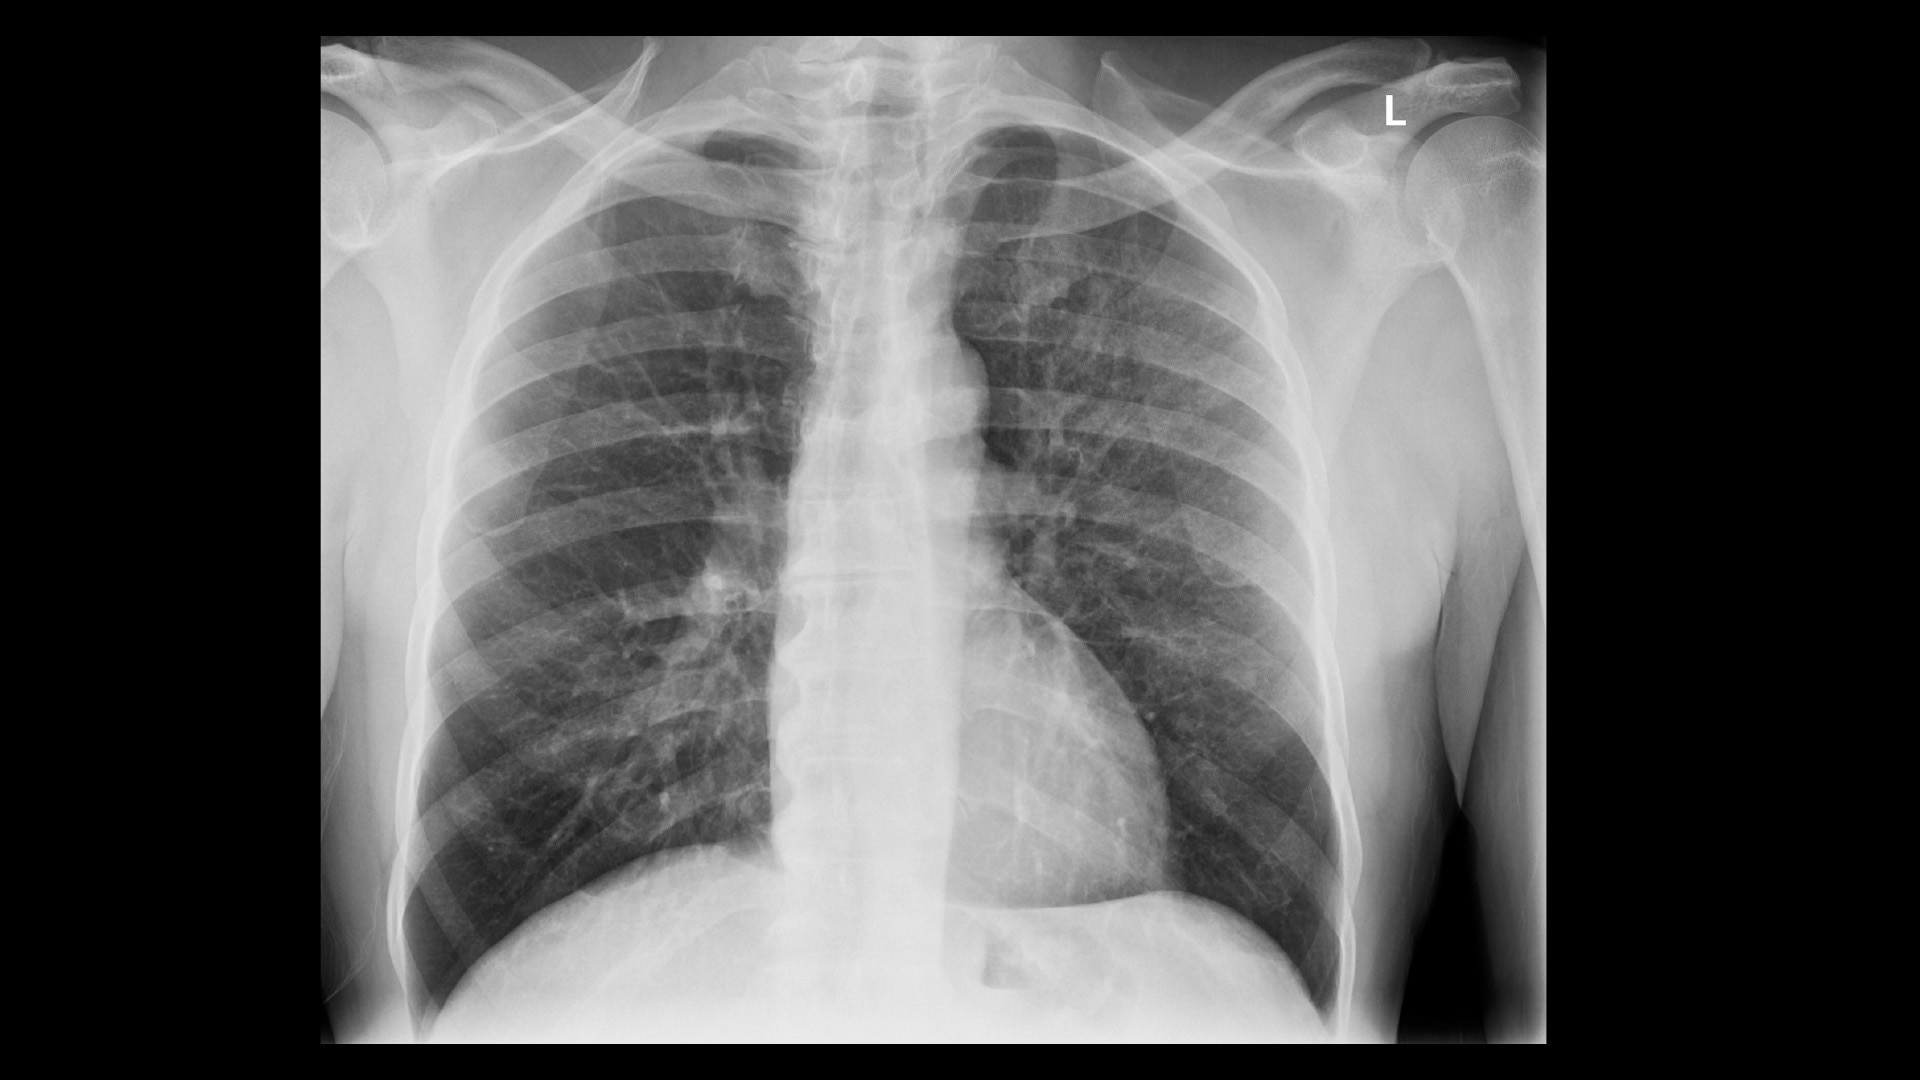

Advanced applications and IQ

Enable radiologists to consistently see more details and provide quality diagnosis